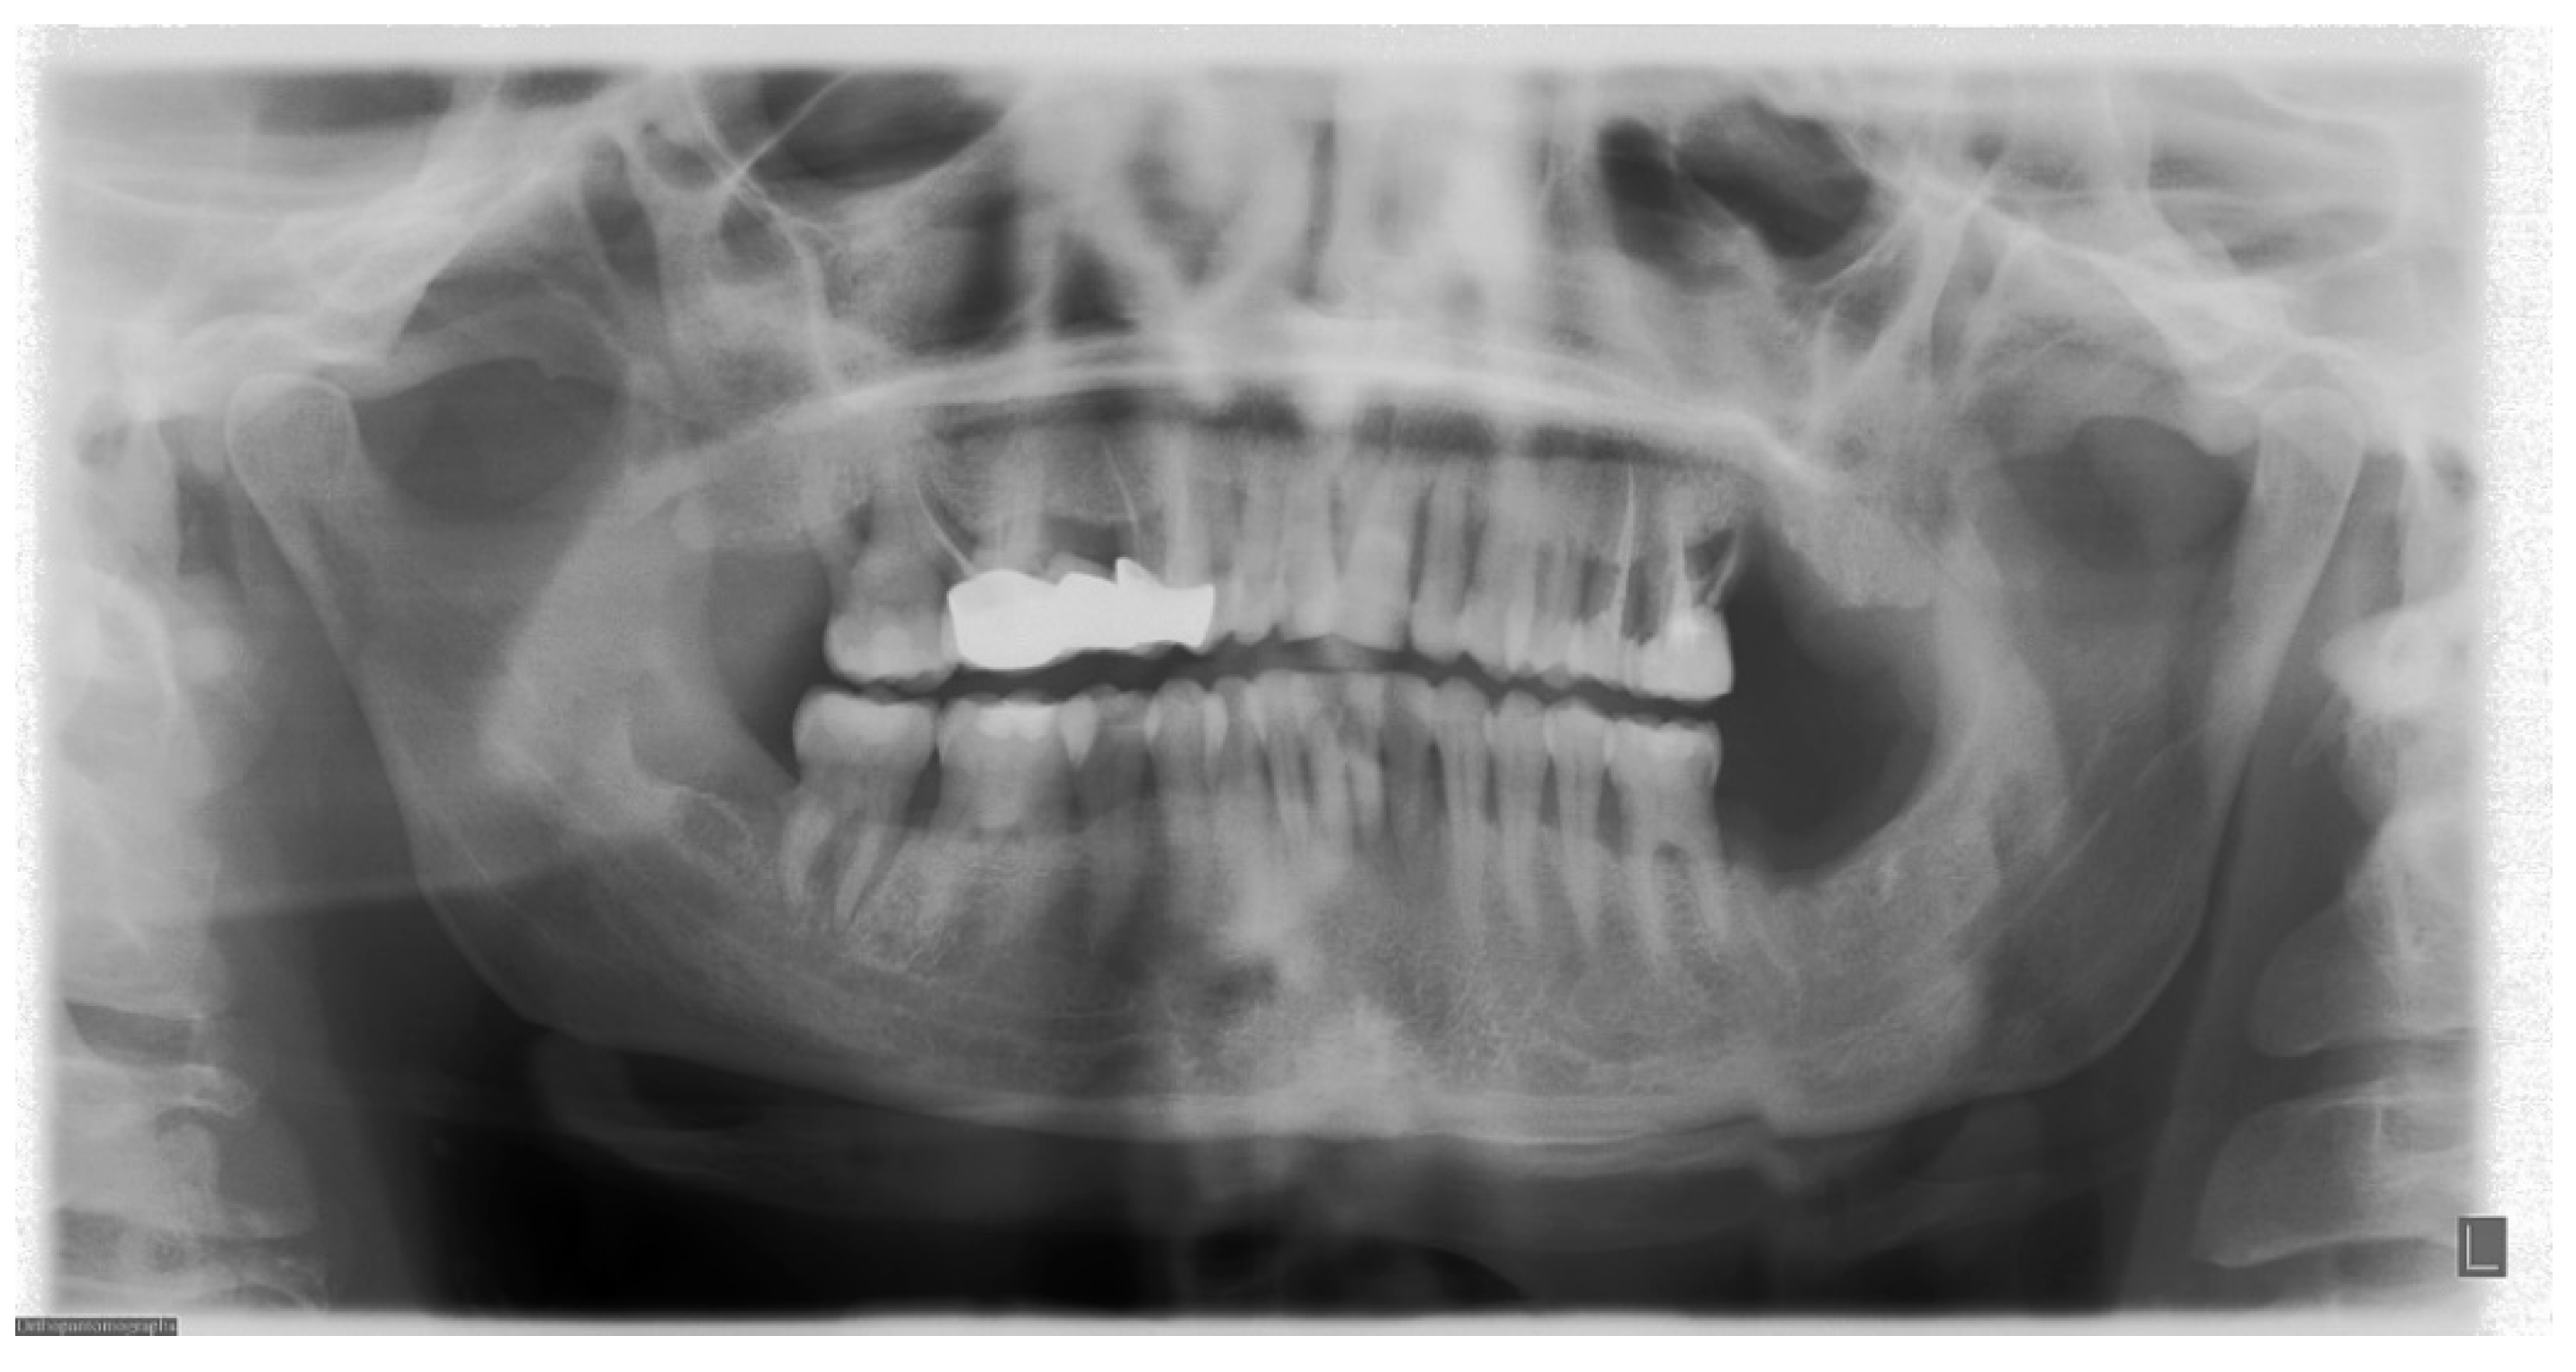

6.2. Inclination of the Occlusal Plane

6.3. Localization of Mandibular Condyles

6.4. Aspect of Upper Teeth Root Apexes

6.5. Position of the Cervical Spine